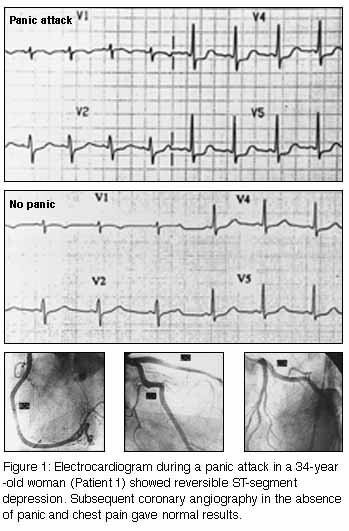

A 34-year-old woman presented to a hospital casualty department in

November 1996 with severe chest pain radiating to her left arm and

shortness of breath after having taken cocaine. She also complained

of palpitations, dizziness, tremor, and an overwhelming sense of

doom and fear. She had taken cocaine occasionally over the previous

two years without panic symptoms. An electrocardiogram (ECG) showed

inferolateral ST-segment depression suggesting ischaemia. The

pain eased with sublingual nitroglycerine and intramuscular

morphine. A thallium exercise stress test two weeks later gave normal

results.

The patient presented again a month later with recurrent episodes of severe chest pain accompanying panic attack symptoms. She had stopped using cocaine after the first panic attack. An ECG taken during persisting pain again showed inferolateral ST-segment depression (Figure 1, below). Serum creatine kinase (CK) levels were normal. Coronary angiography during subsequent hospital admission (when the patient was free of pain) showed a normal coronary arterial tree (Figure 1). The patient was prescribed the selective serotonin reuptake inhibitor paroxetine (20 mg, increasing to 40 mg, daily), low dose aspirin (100 mg daily) and alprazolam (0.5 mg daily). Over two months' follow-up, panic attacks were less frequent, but chest pain recurred with each. After the addition of the slow calcium-channel blocker amlodipine (5 mg daily), her infrequent panic attacks were pain-free. |